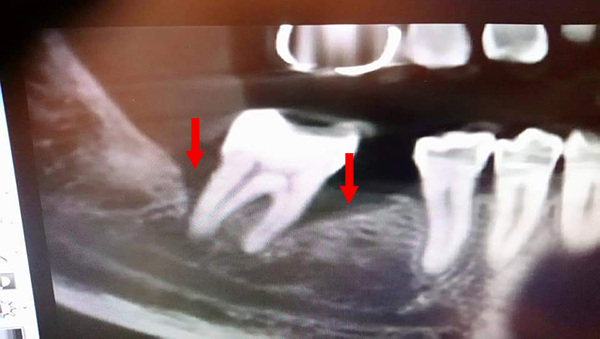

矯正後因牙周病造成骨缺損,電腦斷層上可見明顯骨缺損(紅色箭頭處),經牙周組織再生手術,合併人工骨粉、再生膜及生長因子進行組織重建,術後半年可見明顯之骨再生(黃色箭頭處)。

術前:![]() |

術後:![]() |